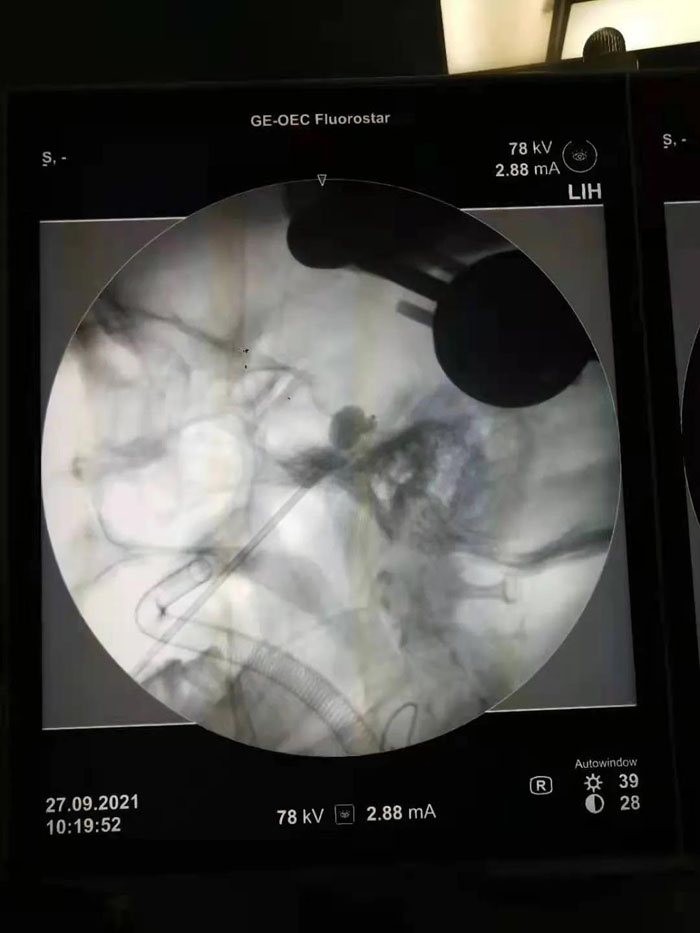

病例1.患者年近八旬,患有三叉神經痛多年,疼痛發作起來痛不欲生,吃飯、洗臉都成了奢望。曾兩次到濟南某省級醫院行射頻、藥物注射等治療,無明顯效果。續繼軍主任團隊術前仔細研判患者病情,認為患者年齡大,開顱手術風險較高。三叉神經半月節球囊壓迫術具有微創、恢復快、費用低的優勢,更適合老年患者及復發患者。但該手術需要精確定位,手術最大的挑戰是要把穿刺針準確穿入近10cm外的卵圓孔,而該孔僅有3mm的大小,難度不亞于射擊比賽中“百步穿楊”。傳統方法只能在C形臂引導下徒手進行,穿刺成功率低。在續繼軍主任指導下,丁鵬、吳開福主治醫師采用機器人輔助穿刺,術前驗證誤差僅為0.37mm,保證了一針穿刺到位,實際術中僅用10秒鐘即完成了穿刺操作,避免了重要血管、腦組織的損傷,大大降低了手術風險。術后,患者面部疼痛即基本消失,2天后順利出院。